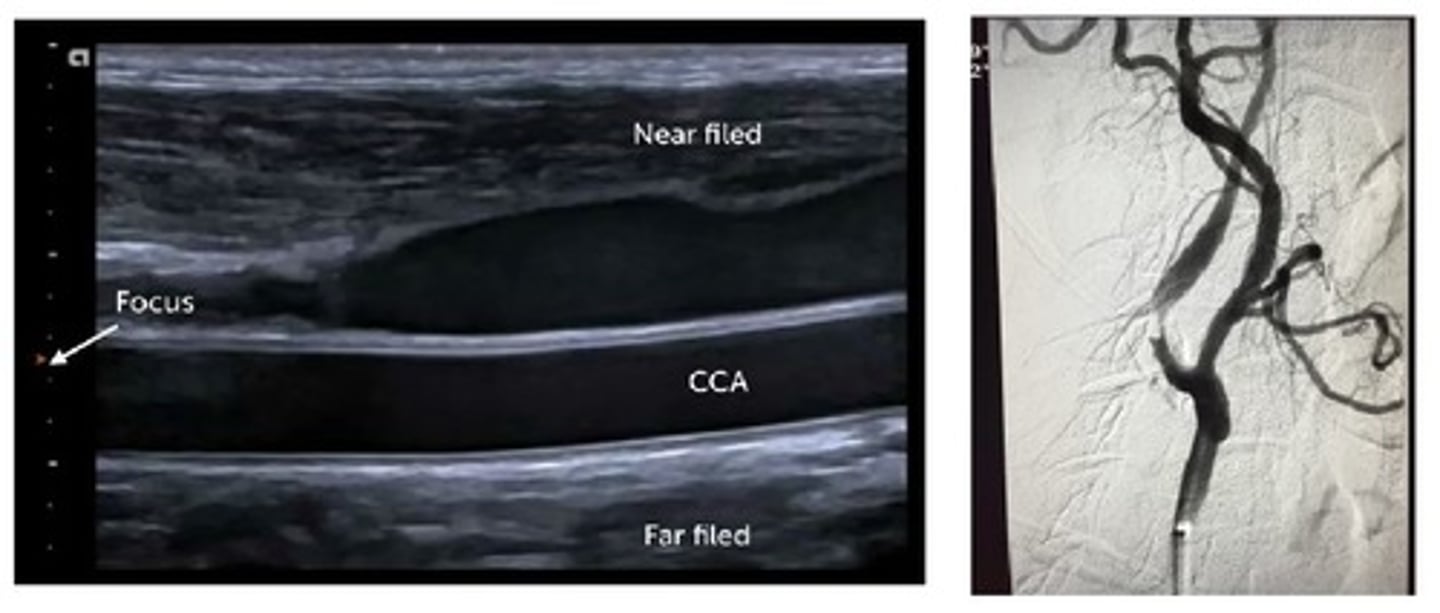

"gold standard"

The "gold standard" in vascular imaging is typically ___, but ideally, vascular ultrasound can match the "gold standard" ___% of the time.

angiography; 100%